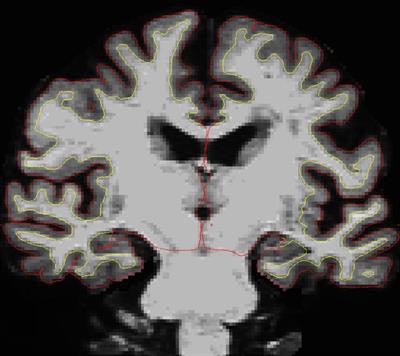

MRI scans were used to measure the thickness of the cortex in 24 SuperAgers and in a control group of 12 age-matched educationally and cognitive-average peers. The annual percent decline in thickness between the first and second MRI exams was 1.06 for the SuperAgers, compared with 2.24 for the control group.